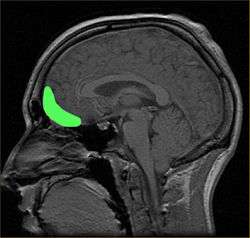

Anatomy and functions